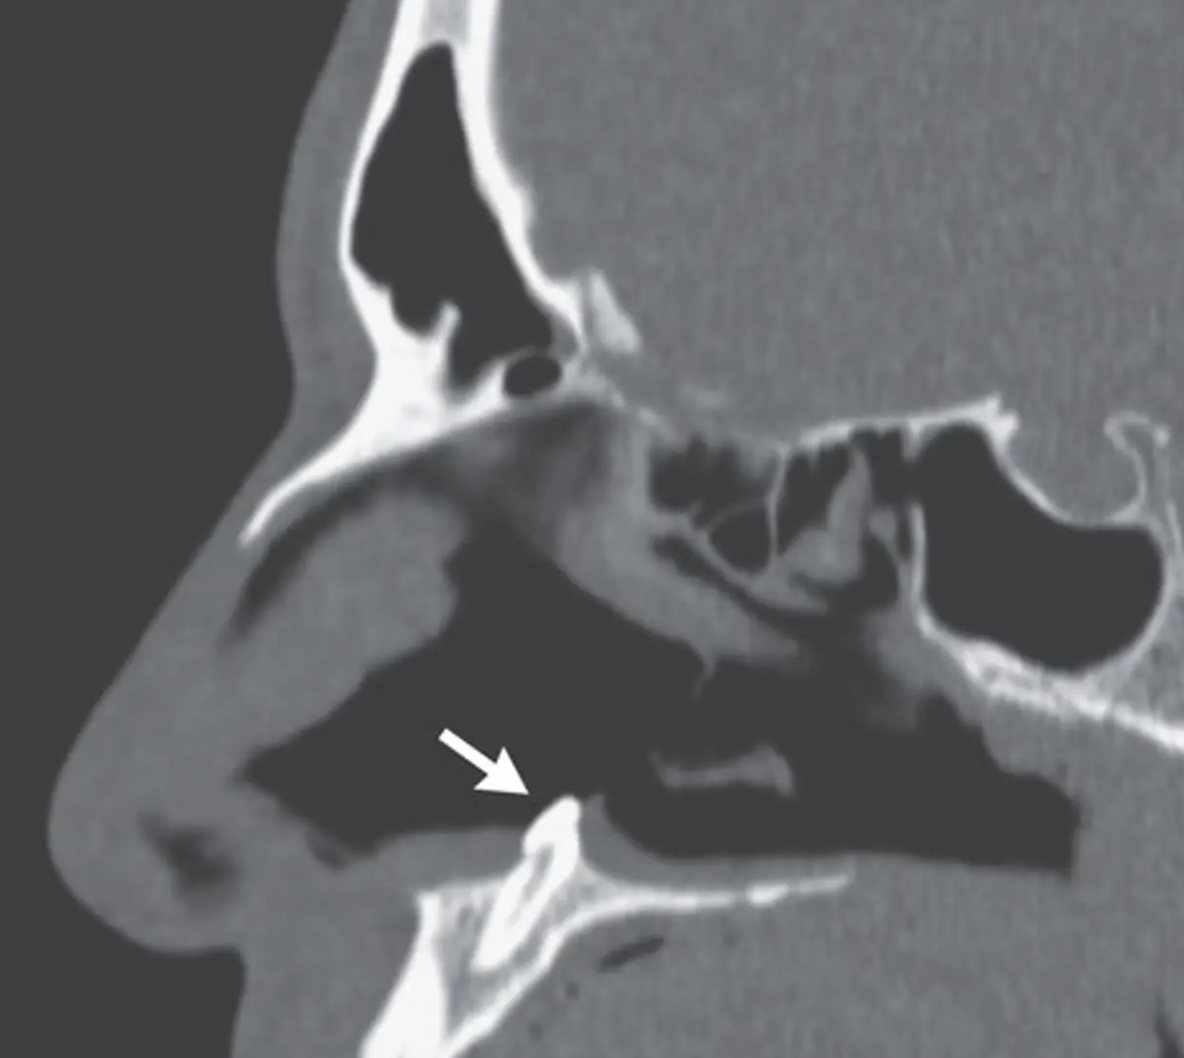

“Computertomografi af bihulerne viste en veldefineret masse, der var i overensstemmelse med en inverteret ektopisk tand i næsehulen. Man mente, at dette kunne forklare de obstruktive symptomer.”

“Tanden blev fjernet under oral og otolaryngologisk kirurgi ved hjælp af en intranasal tilgang. Tanden målte 14 mm i længden, og der var ingen postoperative komplikationer.”